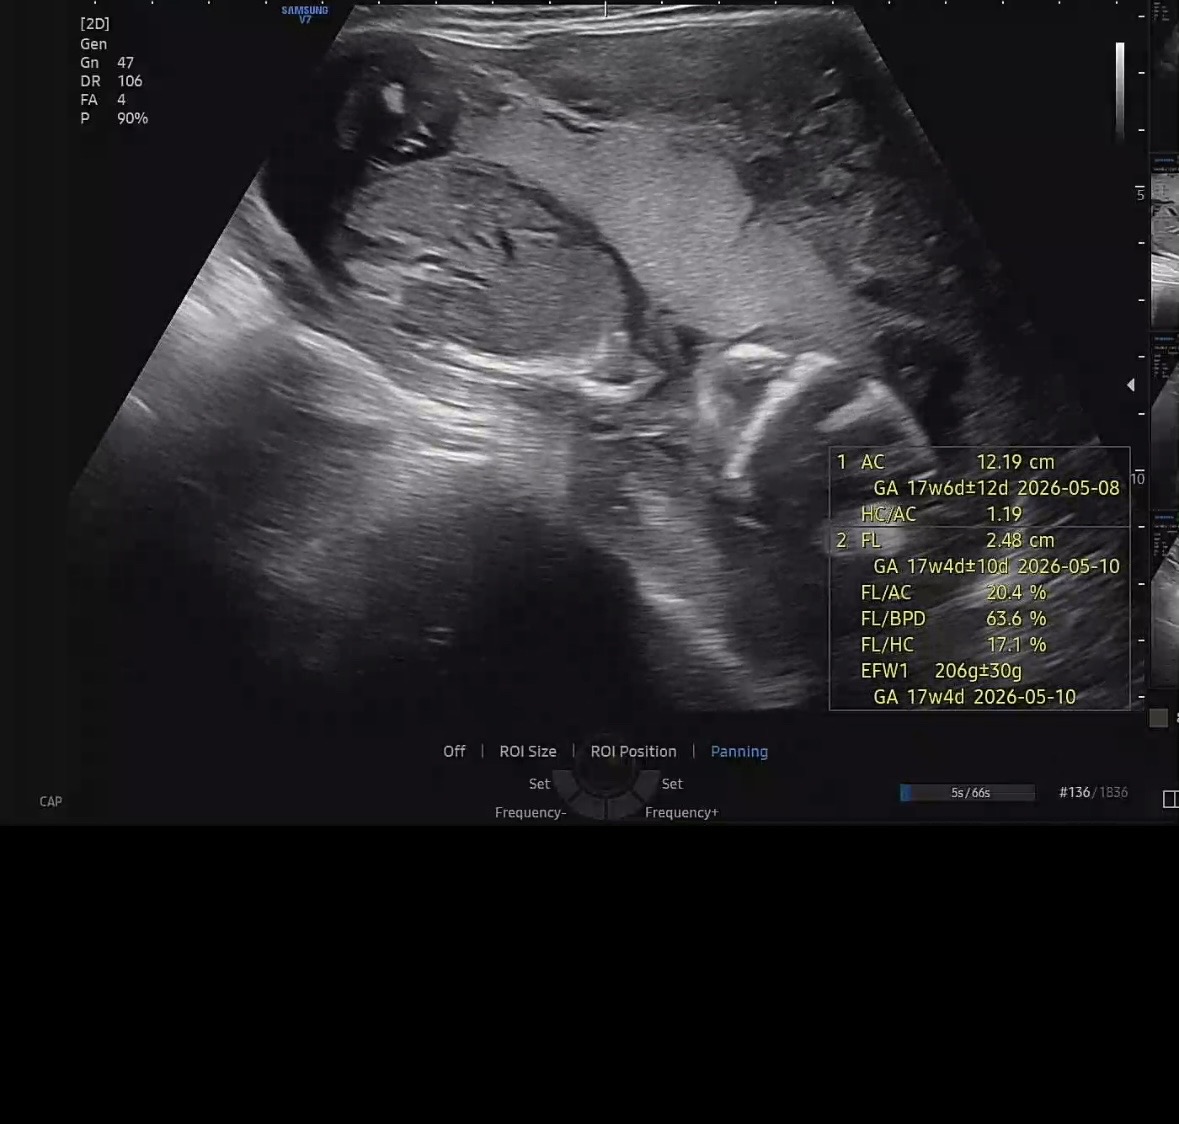

17주차4일 아기가 좁아보인대요

15주차 기형아2차 검사할때부터 양수깊이는 정상이나 가로로 좁아 보인다고 하셨어서 분만병원(대학병원)으로 진료 보라고 권하셔서 4주뒤가 제일 빨라 12말 예약한 상태이고 너무 불안해 17차 오늘 서브 병원 다시 다녀왔는데 저번보다 더 좁아보인다고 하셨어요.. (이번에도 양수 깊이는 정상) 주수에 맞춰서 잘 크고있대요.. 양수적다는 이야기는 많은데 좁아보인다고 하면 검색해도 잘 안나와서요.. 저처럼 이런 이야기 들으신분 있을까요?